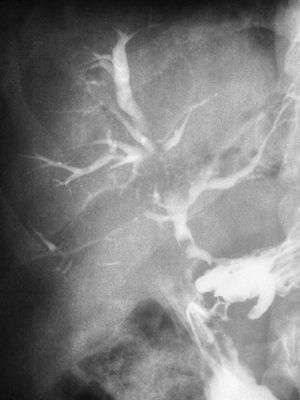

| Abdominal CT with right colocutaneous fistula and associated subcutaneous emphysema. | |